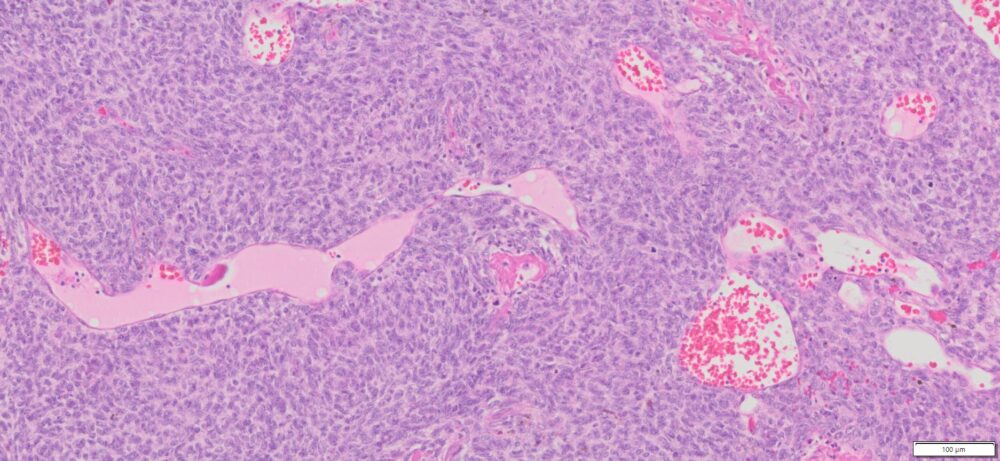

| Tissue | Pathology Diagnosis | Gender/ Age (year) | %Tumor Area | Tumor Grade | TMN/Stage | IHC data |

| Pelvic mass | Human adult pelvic granulosa cell tumor | Female/63 | 90% | II | NA | Calretinin(+), Inhibin (+), AE1/AE3 (+), EMA(-) |